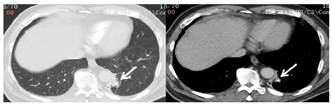

2021年5月8日入院肺部CT显示左下叶基底段嵌有高密度影,其远端阻塞性肺炎表现(图1)。

入院肺部CT显示左下叶基底段嵌有高密度影,其远端阻塞性肺炎。